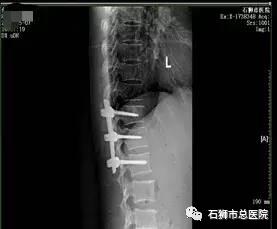

考虑患者近九十岁高龄,常规手术风险难以耐受,且椎体后壁破碎,手术风险极高,经科室内讨论,拟行经皮椎体球囊扩张成形术,术中为进一步减少手术时间,减少手术风险,降低骨水泥经后壁进入椎管风险,予改良行单侧经皮椎体球囊扩张成形术。

术后患者恢复良好,指导功能锻炼,早期腰背支具辅助下起床活动,有效避免了患者卧床并发症的发生。

手术 · 后